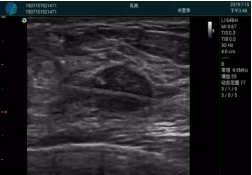

腺體內(nèi)部清晰顯示一低回聲塊影,形態(tài)不規(guī)則,邊界模糊,邊緣呈毛刺狀,內(nèi)部見砂礫樣鈣化

M20引導下穿刺活檢術(shù)

M20引導下平面內(nèi)穿刺取出的腫塊組織